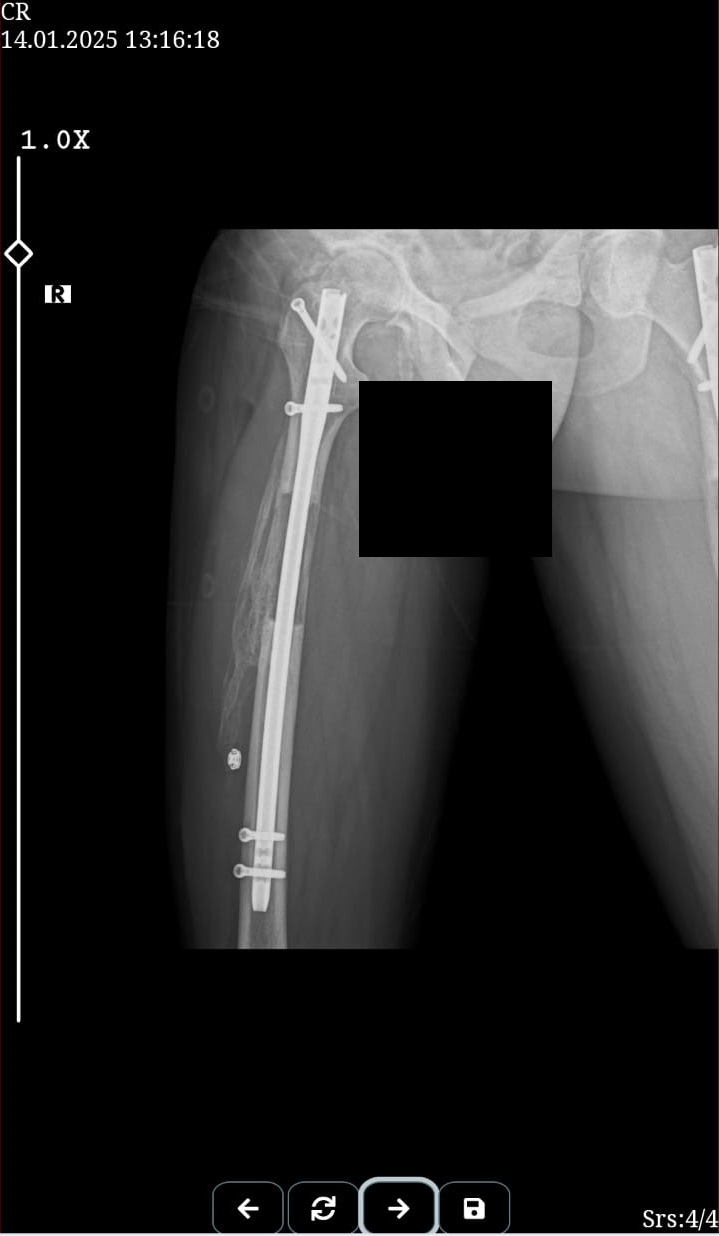

these are just before removing external fixatorAttachments:

This is my after fixator removal xray00 -